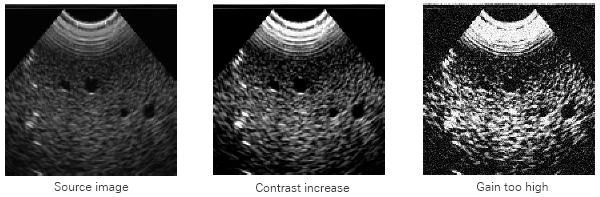

Gain determines the amplification of the CCD's output signal. This parameter may be adjusted manually or automatically. The amplification increases the contrast. A high gain, however, leads to noisy images: